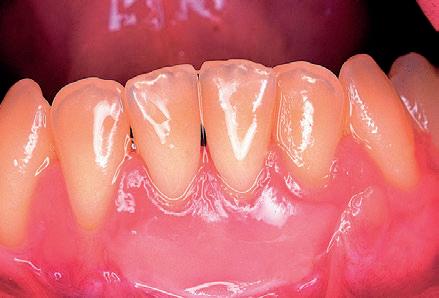

Lo que ocurre en este primer caso, al estar ya descrito en la literatura cientí ca, es el menos sorpresivo de los cuatro casos que se presentan. Sin embargo, no por ello deja de ser un fenómeno, en mi opinión, llamativo. Para interpretarlo correctamente, nos tenemos que situar a principios de la década de los noventa. La paciente S. G. de 26 años, desarrolló recesiones gingivales a nivel de 31 y 41 (Fig. 1). En aquella época, una de las técnicas quirúrgicas más frecuentemente empleada para el cubrimiento de las recesiones gingivales era el autoinjerto libre epitelizado, descrito por Holbrook y Oshenmbein en 1983.

Fig 1: Año 1990. Mujer de 26 años que presenta recesiones gingivales a nivel de 31-41.